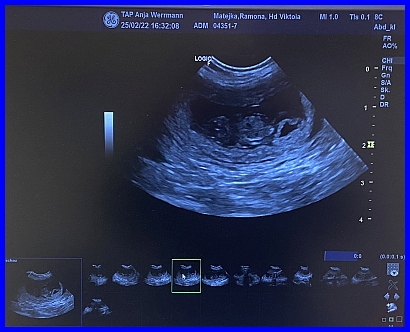

Da sind sie, Zwillinge :-) die ersten Babys!

Hier ist ganz eindeutig eine gefüllte Fruchtblase zu erkennen, links ist das kleine Köpfchen und die "Kugel" in der Mitte der Fruchtblase, ist der Körper des Fötus.

Es ist der 29. Tag der Trächtigkeit. Viktoria fand es ziemlich blöd auf dem Tisch, das sieht man ihr auch deutlich an.